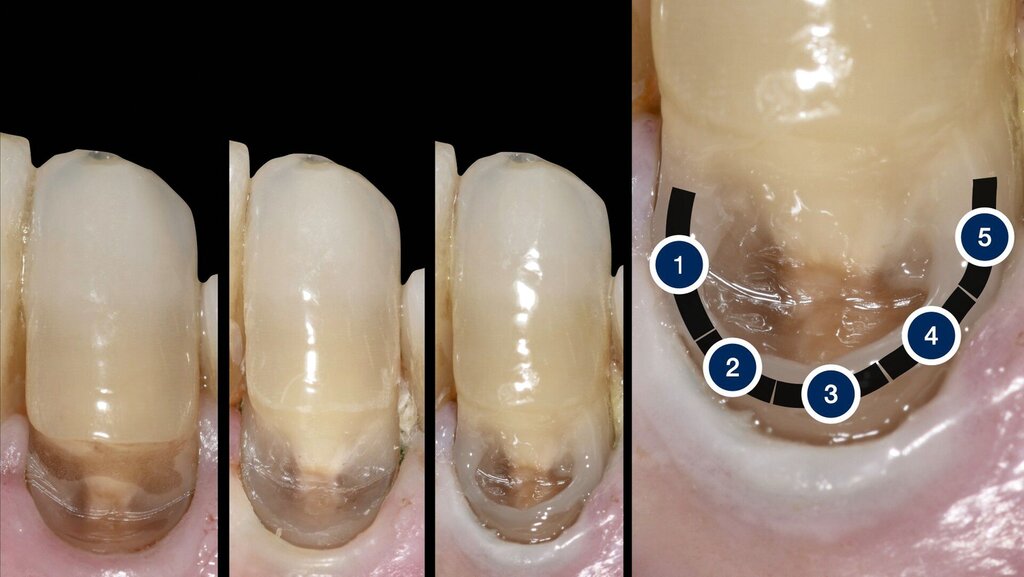

Die Vorgehensweise bei der BERK®-Technik wird am Fall des Eckzahns 33 genauer dargestellt. Die Ausgangssituation zeigt einen tiefen zervikalen Defekt mit zervikal epigingivaler Randbegrenzung (Abbildung 2a). Nach Legen eines Retraktionsfadens lag der gesamte Rand der Kavität supragingival und war gut zugänglich (Abbildung 2b).

Im nächsten Schritt wurde ein fließfähiges Komposit unter Verwendung einer dünnen Luer-Lock-Applikationskanüle vom Typ 45 (Innendurchmesser circa 0,25 mm) portionsweise auf den zervikalen Kavitätenrand aufgetragen (Abbildungen 2c und 2d). Dabei erfolgte das Aufbringen des fließfähigen Komposits in circa fünf kleinen Portionen. Nach Aufbringen der ersten Portion erfolgte eine kurze Lichthärtung für circa 2–3 Sekunden. Anschließend erfolgte das gezielte Auftragen der zweiten Portion, wieder gefolgt von einem kurzen Lichthärtungsimpuls.

Nach diesem Schema wurden weitere Portionen des fließfähigen Materials appliziert, bis eine Art „Wanne“ im zervikalen Bereich ausgeformt war. Nach Aufbringen der letzten Portion wurde eine Lichtpolymerisation von 20 Sekunden vorgenommen. Im Anschluss daran konnte hochviskoses Kompositmaterial mit einem kleinen Spatel in die Kavität appliziert und abschließend für 20 Sekunden lichtpolymerisiert werden (Abbildung 2e).